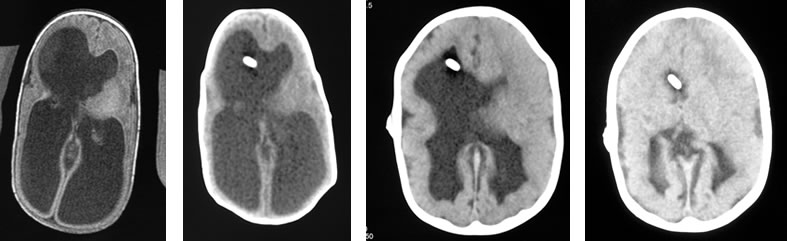

(1)CTスキャン

CTスキャンで脳室拡大を認めることが水頭症の診断の第1ステップになります。得られる情報量の多さと検査の受けやすさを考えると第1選択の検査法になります。

左:胎児MRIで診断された水頭症

中:脊髄髄膜瘤に伴う水頭症

右:中脳水道閉塞による水頭症

(2)MRI(磁気共鳴画像診断)

水頭症に伴う脳形成不全の診断や水頭症の原因となる脳腫瘍などの診断に用います。

CTスキャンより圧倒的に情報量が多いので、治療前にMRIを撮影することが一般的です。一方、8歳未満の小児では鎮静を要することが多いという欠点があり、バランスをよく考えて選択される検査法です。